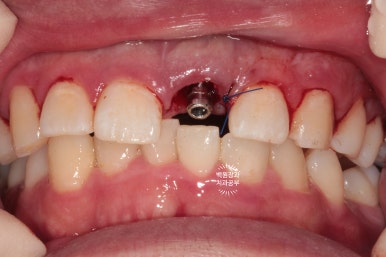

40대 남자 환자분이셨고, 처음 뵈었을 때 왼쪽 위 대문니가 이미 부러진 상태로 오셨었어요.

엑스레이를 보시면, 내원 당시 기둥까지 빠졌던 치아를 그 자리에 끼워놓으셨기 때문에 마치 치아가 멀쩡한 것 처럼 보입니다만, 이미 사용하기 어려운 지경의 상태였습니다.

이런 중절치 부러짐은 은근히 많이 볼 수 있는 증례입니다.

입천장 쪽에서 바라보았을 때, 이미 잇몸라인보다 깊은곳까지 부러져 있는 뿌리만 남은 치아를 보실 수 있어요.

예전에 신경치료를 해놓은 치아라 앞니 뿌리가 이미 검게 변해버린 상태입니다.